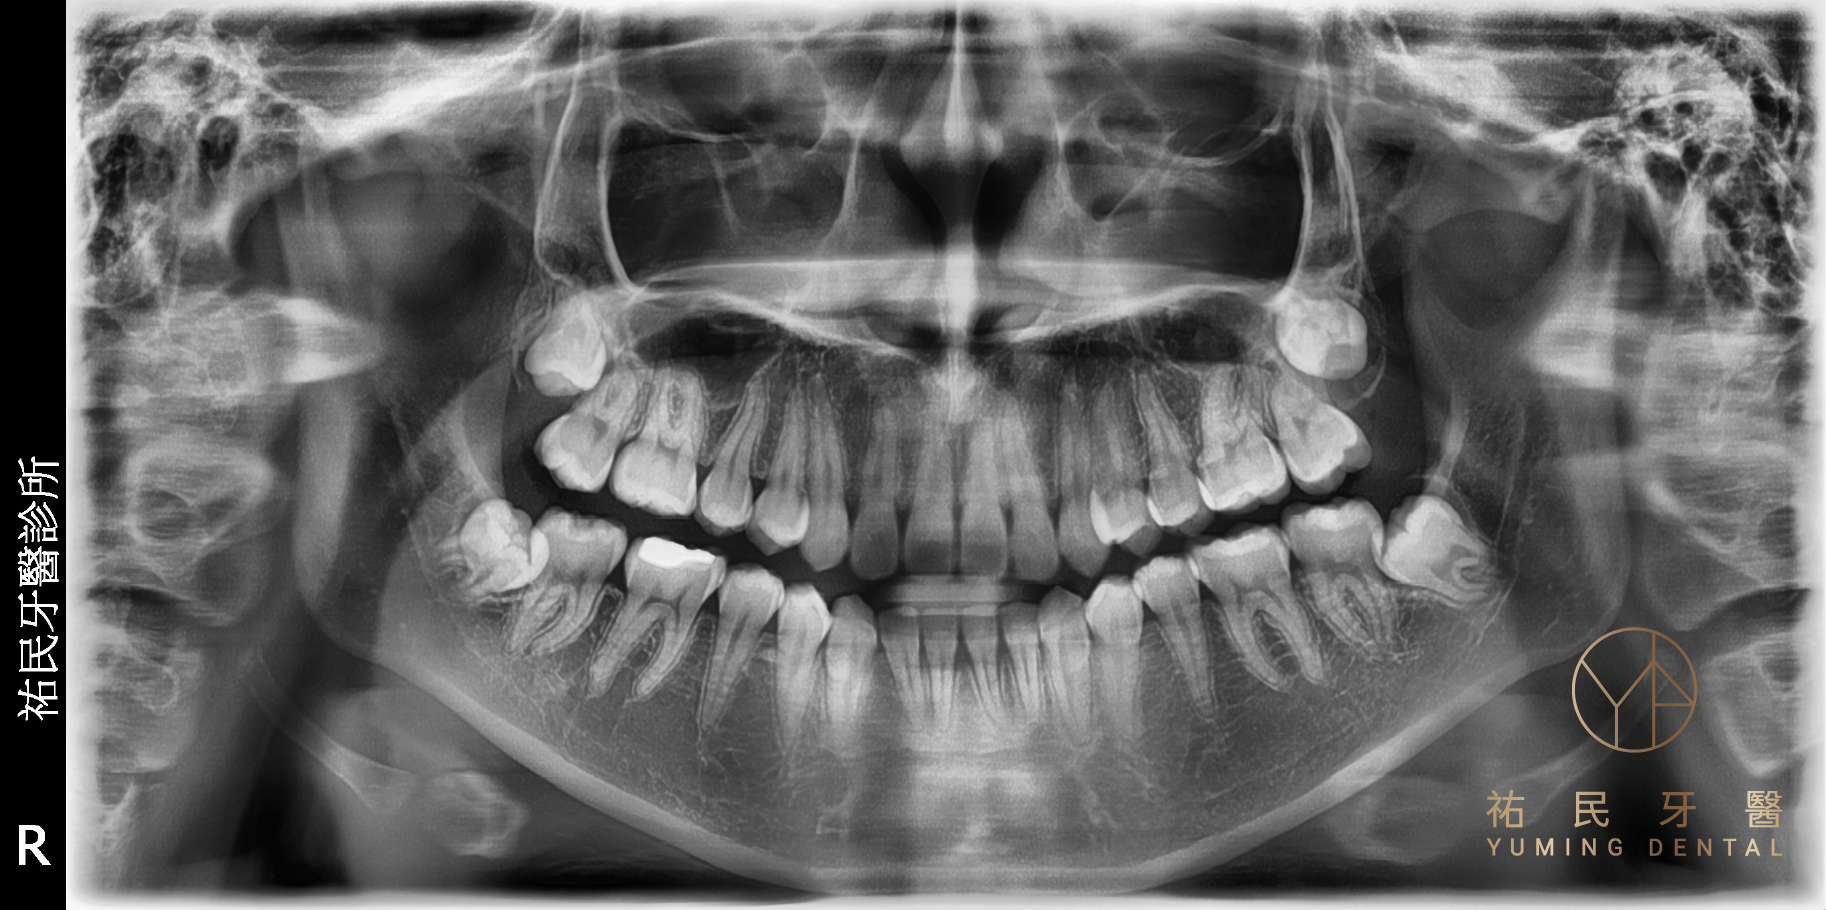

大約在 9~10 歲時,就能從 X 光片中看到智齒的牙胚。智齒萌發的時間通常在 17~25 歲左右,這時人的生理與心理智慧都逐漸成熟,因此取名為智齒。

大約在 9~10 歲時,就能從 X 光片中看到智齒的牙胚。

| 完全埋伏型 | 完全埋在齒槽骨內,X 光才看得見 | 需個案評估 | 未擠壓神經或鄰牙可追蹤觀察;若形成囊腫則必須手術 |